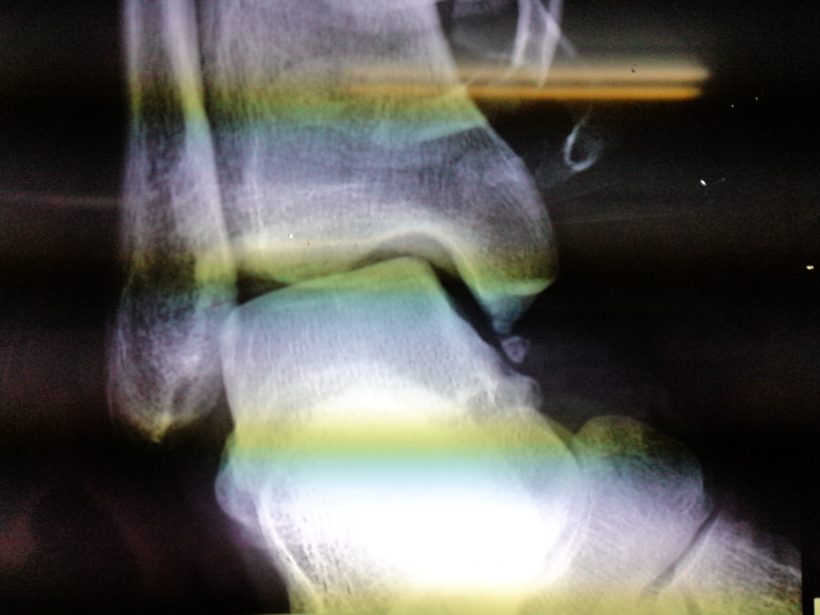

筋が支えられずに足首から下の骨が曲がっている&謎の小骨がポッキン

している事が判明してダブルショーック!!